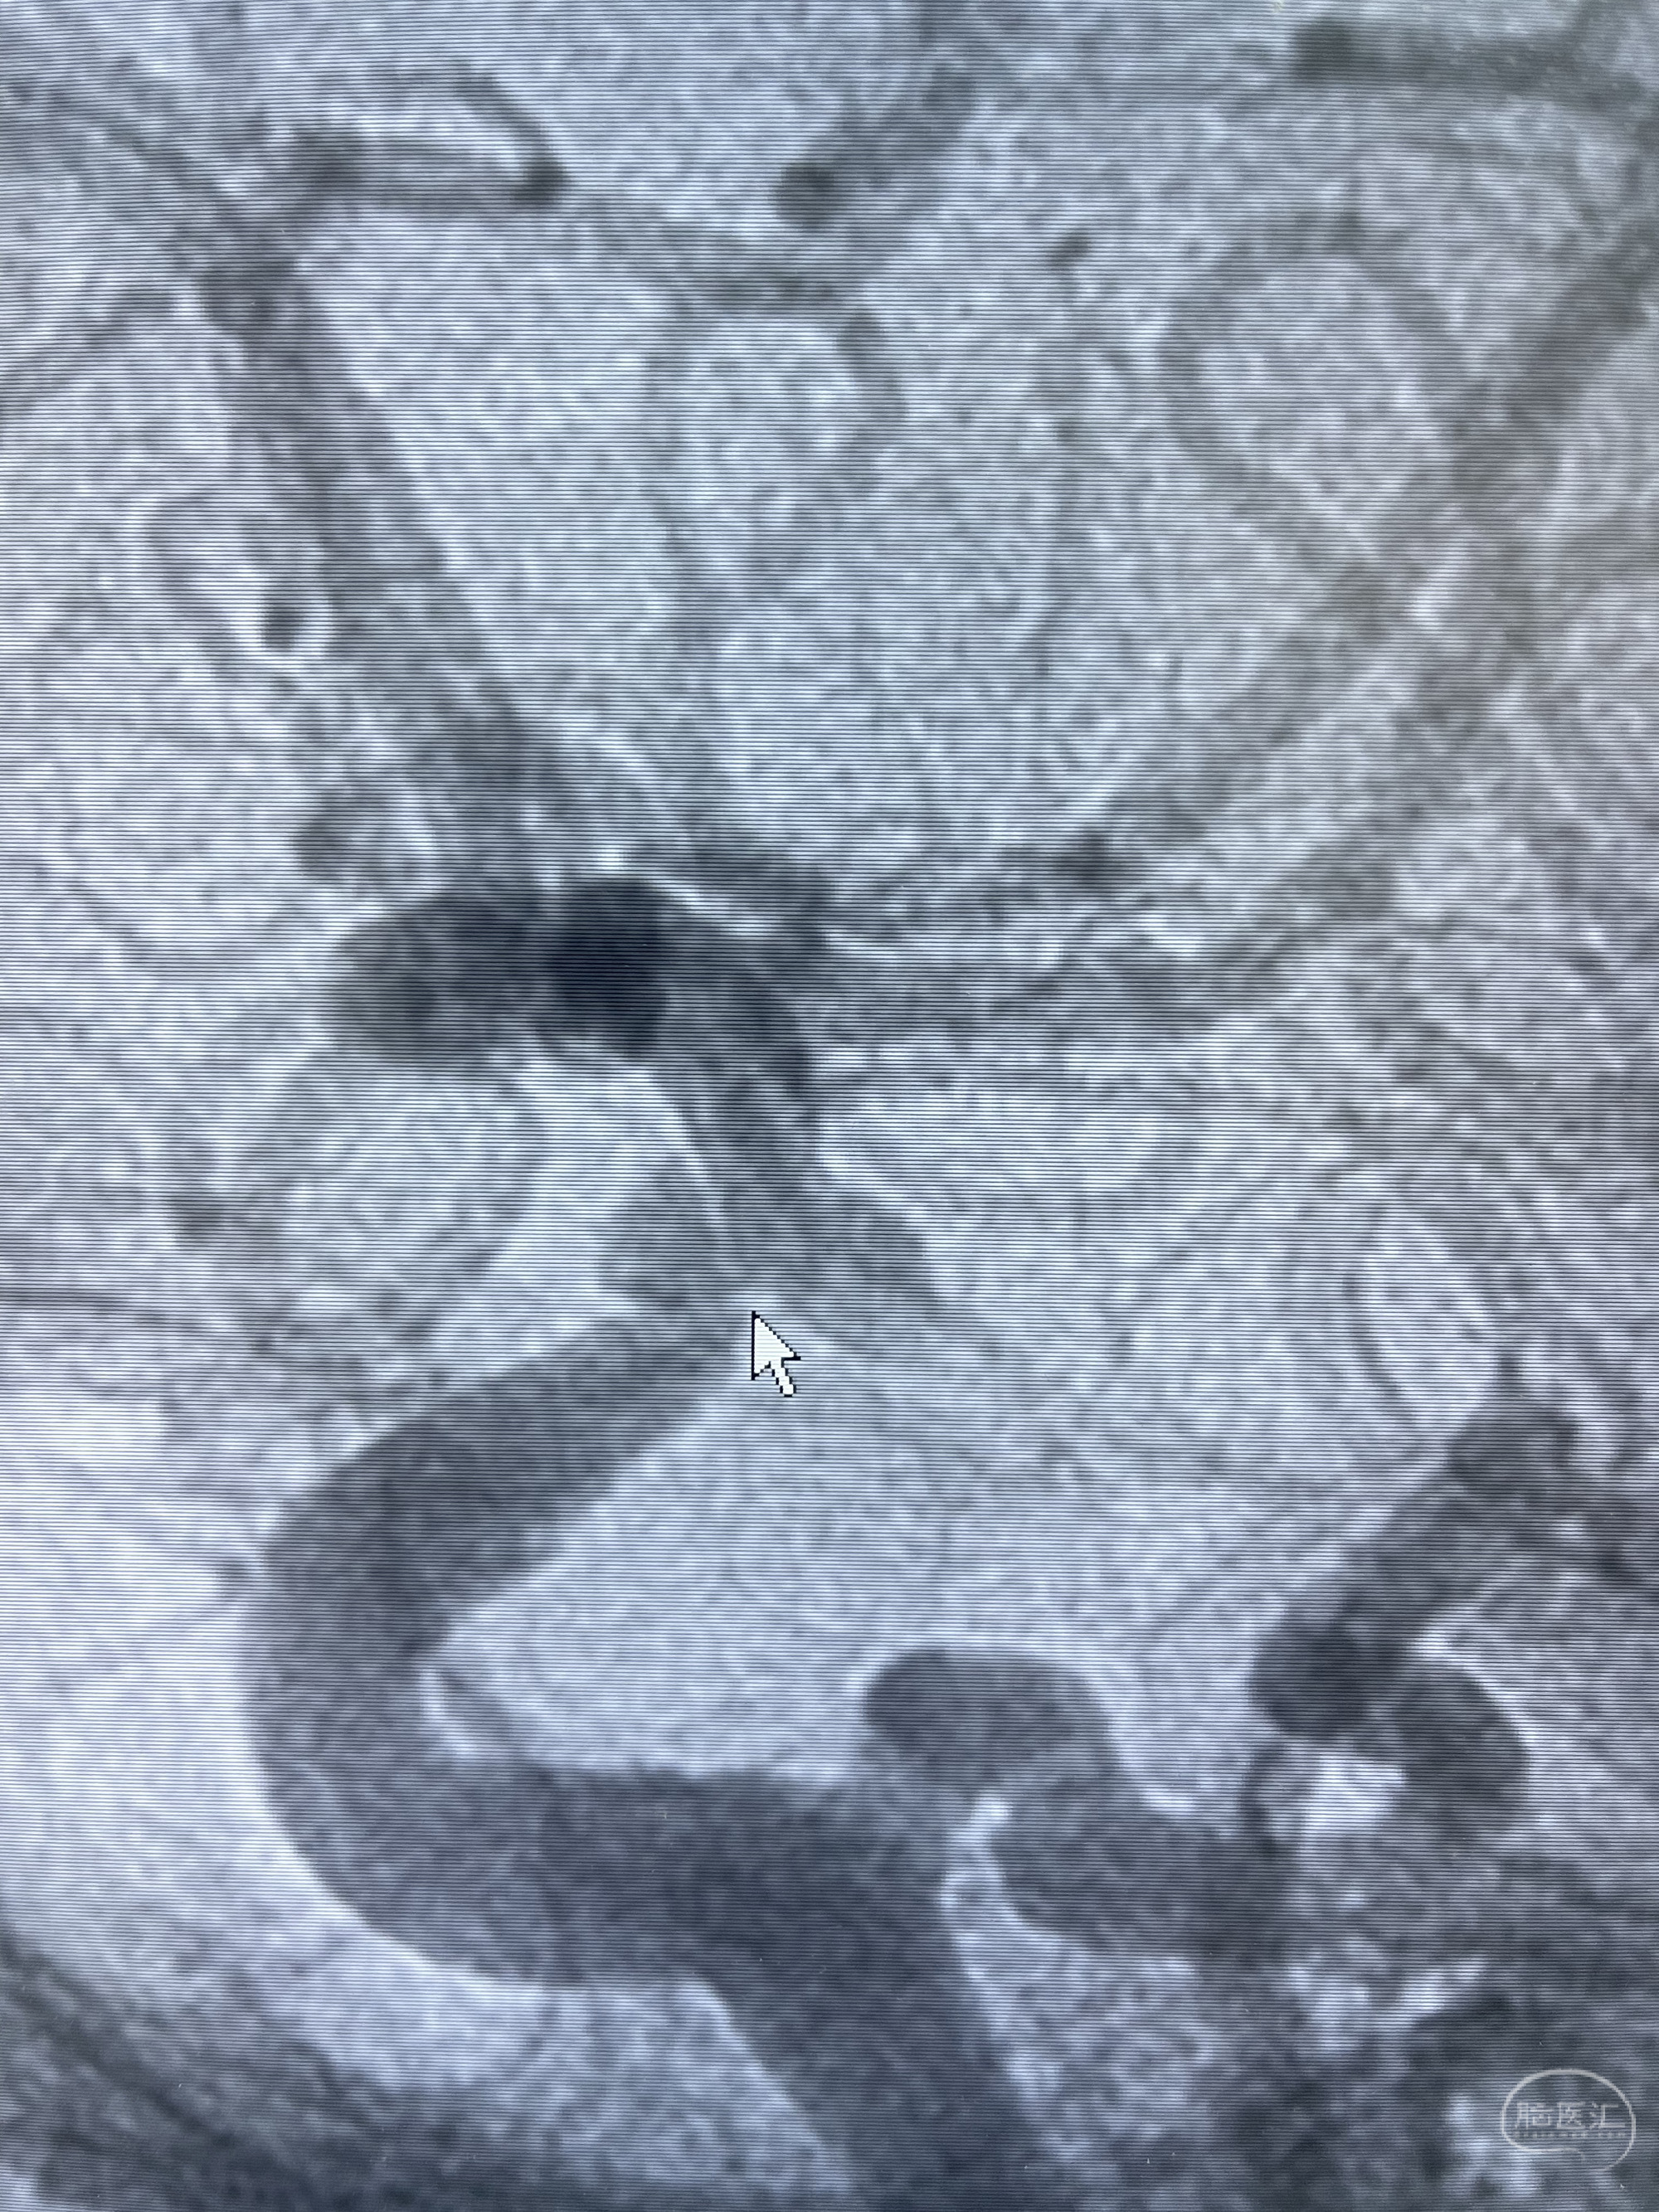

脑血管造影2023.03.06:右侧颈内动脉颈段至岩骨段闭塞,可见后后循环通过原始三叉动脉吻合代偿至海绵窦段,后交通区可见囊状造影剂填充影,左侧锁骨下动脉呈“残端”改变,呈“右侧颈总动脉支架成形术后改变”,支架内血流通畅,可见后交通吻合显影至左侧大脑后动脉,并可见左枕动脉吻合椎动脉至锁骨下动脉

2023-03-06DSA:

1.右侧颈内动脉及左侧锁骨下动脉闭塞

2.右侧颈内动脉由后循环经右侧后交通动脉前向代偿显示

3.右侧颈内动脉眼动脉段近后交通动脉处重度狭窄伴前壁不规则动脉瘤

4.右侧颈外动脉可见经由右侧脑膜中动脉吻合显影右侧眼动脉及颈内动脉

5.左侧颈总动脉起始部支架术后

6.左侧颈外动脉可见吻合显影至左侧椎动脉并逆行供血至左侧腋动脉

7.左侧锁骨下动脉闭塞

1.箭头处为右侧颈内动脉后交通动脉处重度狭窄,狭窄前壁为不规则动脉瘤;

2.狭窄远端颈内动脉由左侧颈内动脉经左侧后交通动脉—基底动脉顶—右侧后交通—右侧颈内动脉—右侧大脑中动脉途径代偿

左侧颈内动脉经左侧后交通动脉—基底动脉顶—右侧后交通—右侧颈内动脉—右侧大脑中动脉途径代偿